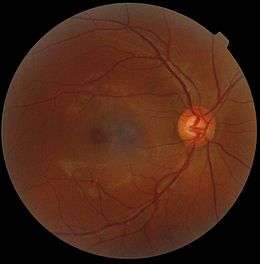

The interior of the posterior half of the left eyeball. A fundus photograph showing the macula as a spot to the left. The optic disc is the area on the right where blood vessels converge. The grey, more diffuse spot in the centre is a shadow artifact.

A fundus photograph showing the macula as a spot to the left. The optic disc is the area on the right where blood vessels converge. The grey, more diffuse spot in the centre is a shadow artifact.